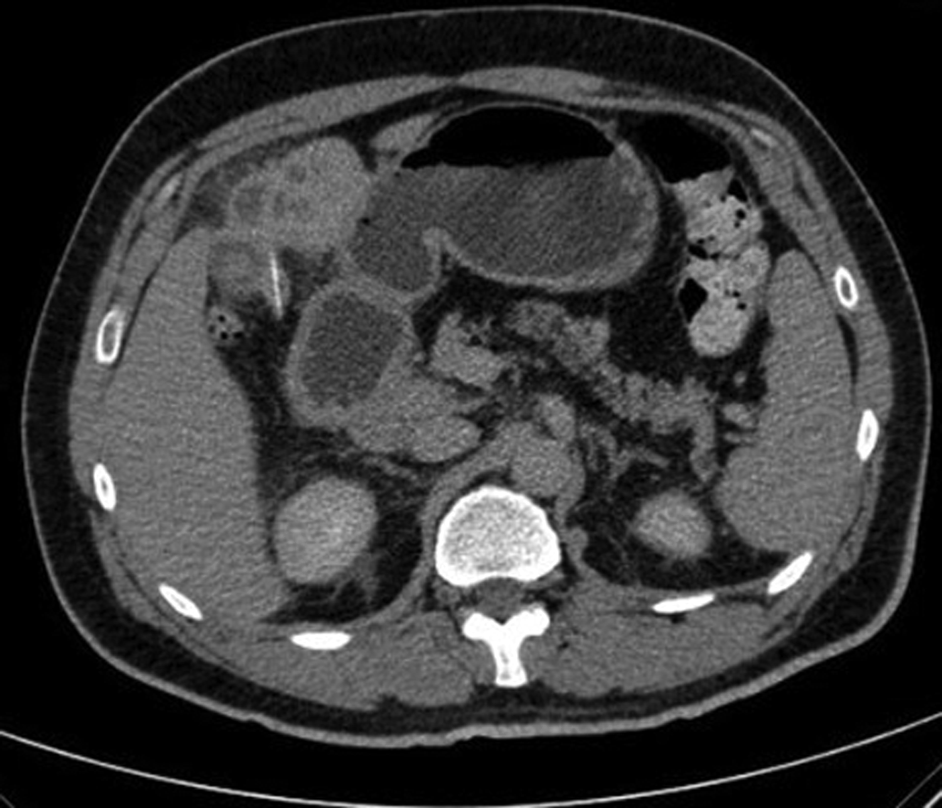

一個月後,阿卜杜勒再次被高燒和劇烈的腹痛擊倒。這一次,情況似乎更嚴重了。他的白細胞計數飆升,肝功能檢查顯示異常。更令人不安的是,CT掃描揭示了一個令人震驚的事實:他肝臟裏竟然藏着一根2.5釐米長的針狀異物!

CT掃描顯示,肝臟第四段有一個5.6釐米×7.5釐米×7.7釐米的膿腫,而那根“針”赫然是一根魚刺!

腹部 CT 掃描顯示肝臟左葉有異物 圖源:文獻